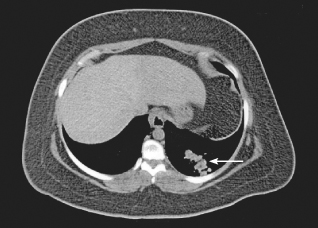

acute cholecystitis

Ronald N. Rubin, MD

<p>A 50-year-old woman is hospitalized after she presents with abdominal pain. The pain is episodic and is located in the epigastric area and toward the right upper quadrant (RUQ). It awakened her...